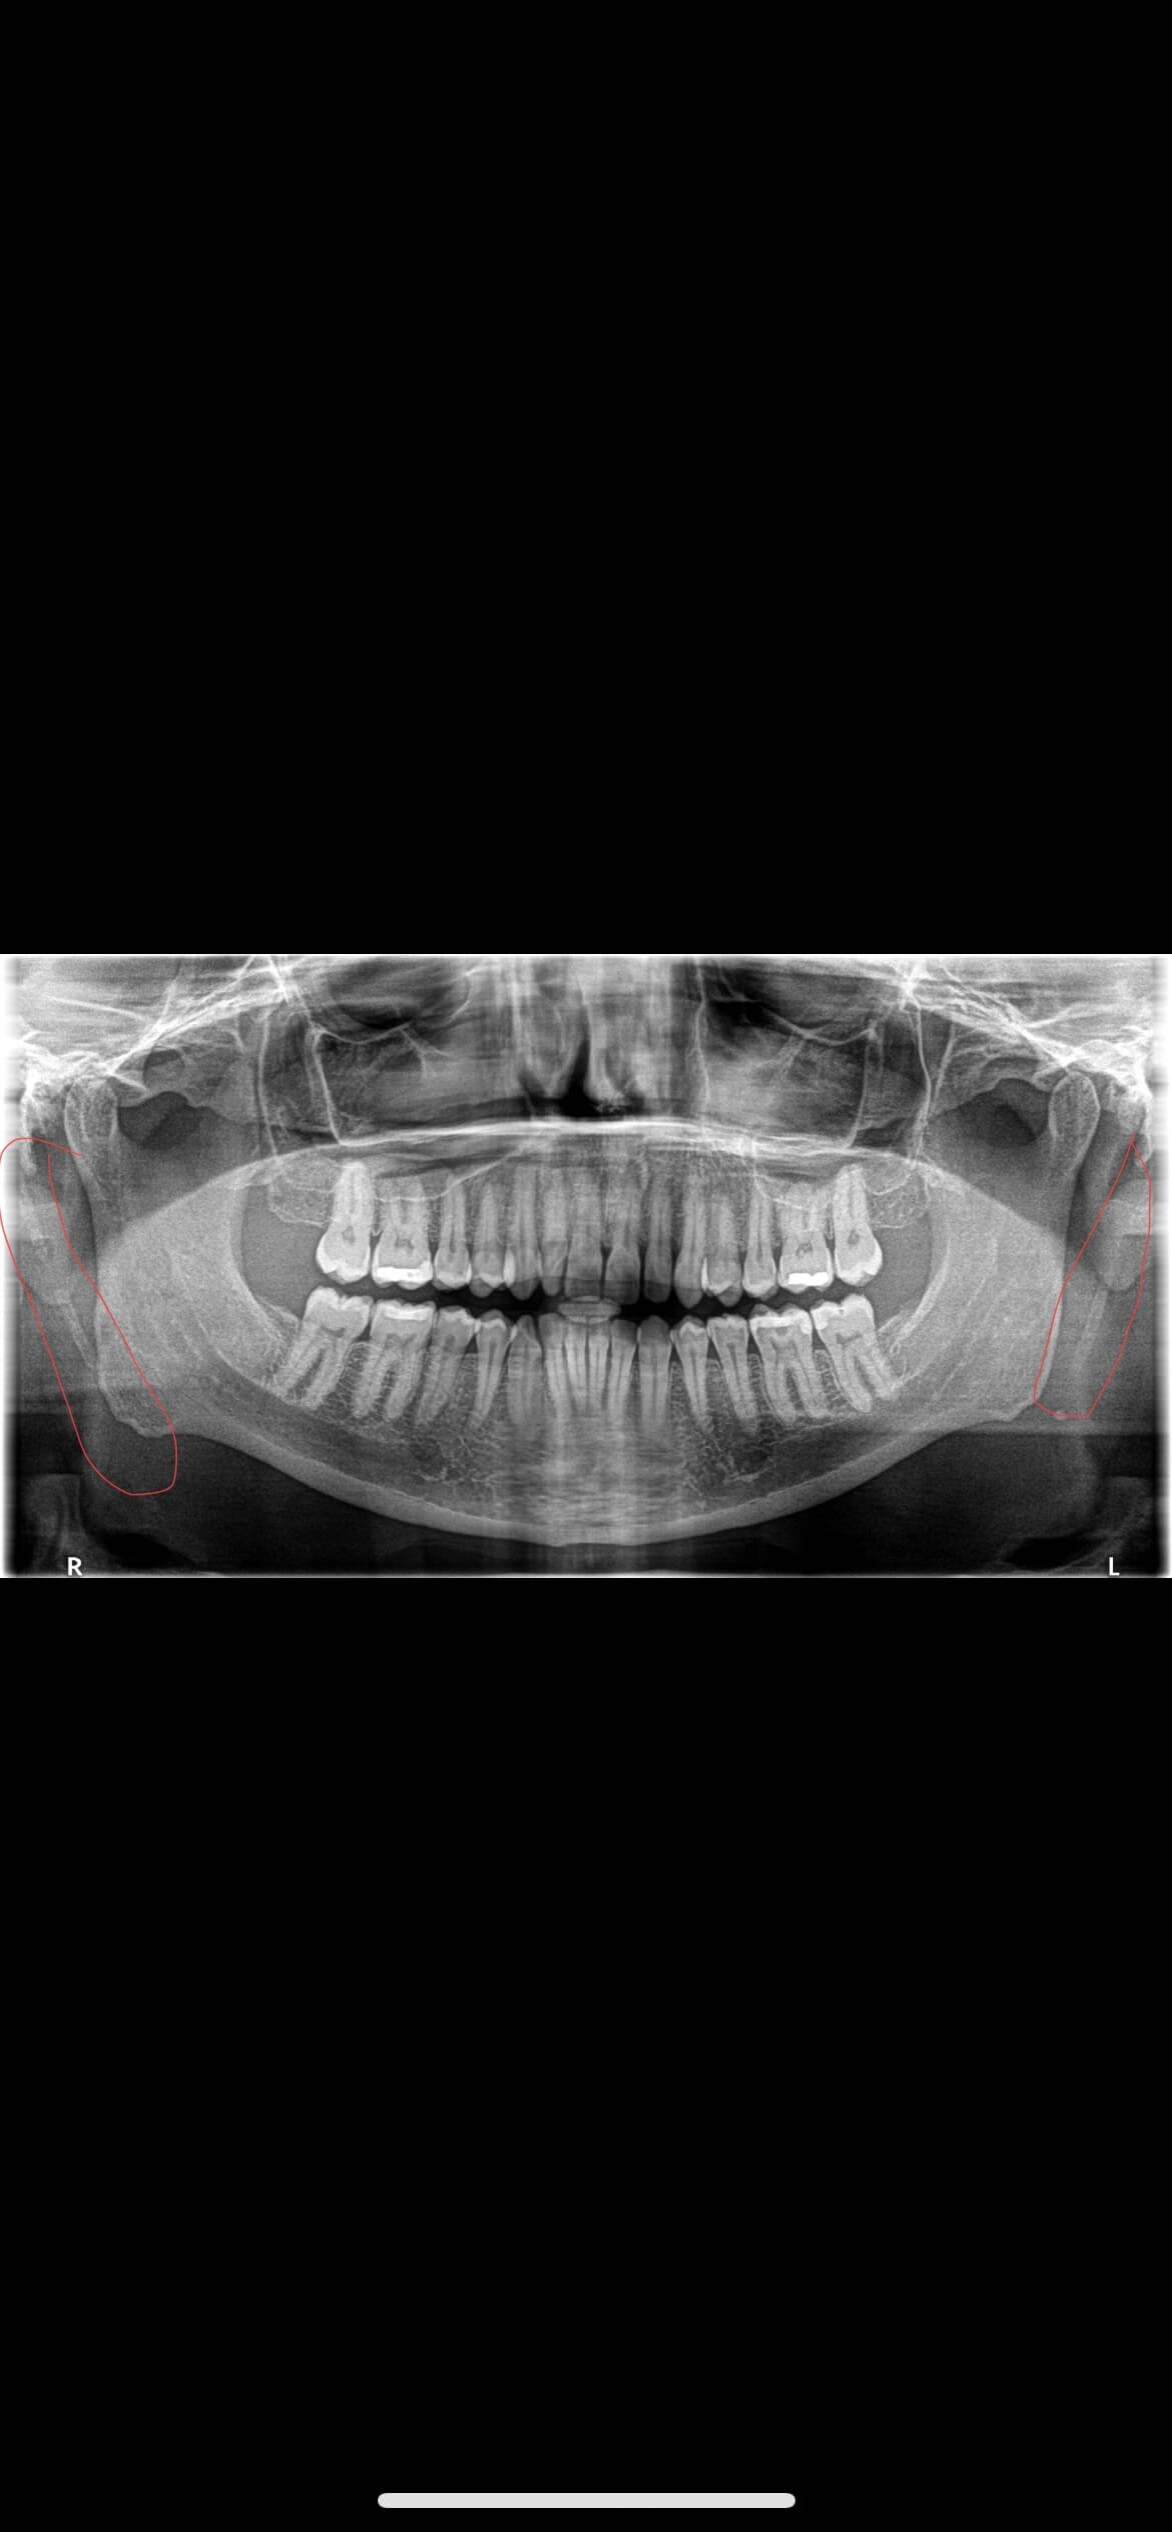

I have attached annotated xray pointing out your elongated styloids /calcified stylohyoid ligament.

Do you have access to your CT? I can see how close your styloids are to C1 and assess for any IJV compression